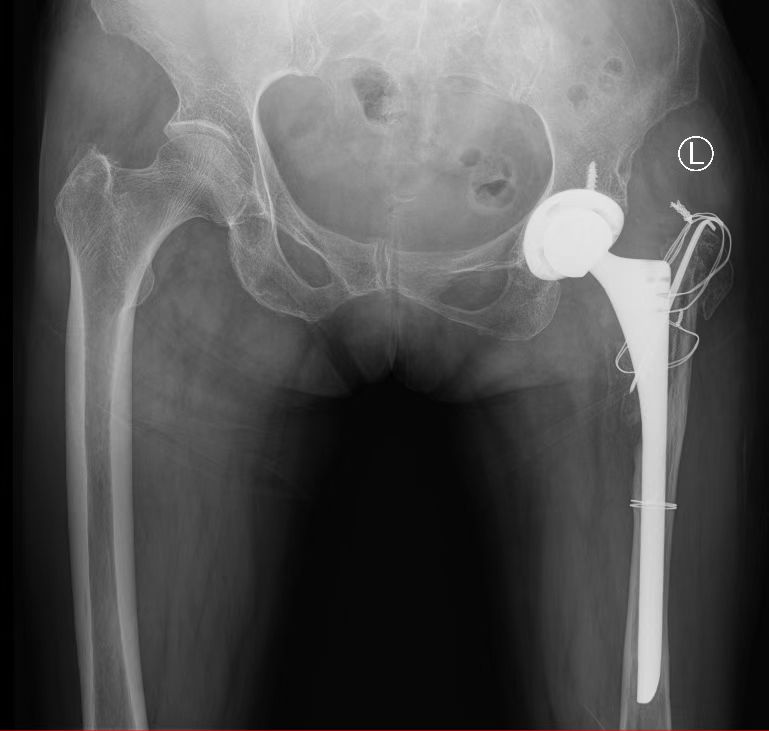

2022年3月,吕阿姨在家人的鼓励下就诊于我院髋关节外二科,由于复杂的病情,李红军主任团队为她量身定制了手术方案,经过医患双方的共同努力,吕阿姨获得了良好的生活质量。“因为身体的残疾,在社会上经常会遭受别人异样的目光,心理很自卑,现在终于过上了正常人的生活!”吕阿姨兴奋的说。

髋关节外二科团队近年来勇攀高峰,立足我院国家级诊疗中心平台,完成了一个个高难度手术,对复杂髋关节发育不良初次置换、巨大骨缺损的髋关节翻修、髋关节感染的一期翻修,以及基于精细化诊断的髋关节部分翻修积累了丰富的经验。